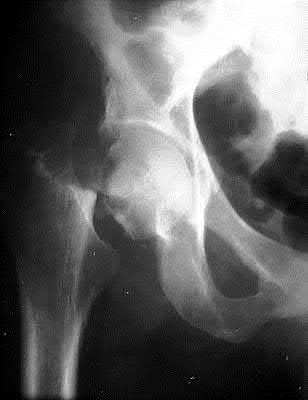

A 12-year-old obese male presents with a stable slipped capital femoral epiphysis (SCFE) of the left hip. Which of the following factors is the strongest indication for prophylactic in situ pinning of the asymptomatic contralateral right hip?

Correct Answer: Presence of an underlying endocrine disorder (e.g., hypothyroidism)

Explanation:

Prophylactic pinning of the contralateral hip in SCFE is controversial but is strongly indicated in patients with a high risk of bilateral involvement. Risk factors predicting contralateral slip include an underlying endocrine disorder (such as hypothyroidism, panhypopituitarism, or renal osteodystrophy), prior radiation therapy, or age of presentation less than 10 years (or low modified Oxford bone age score).